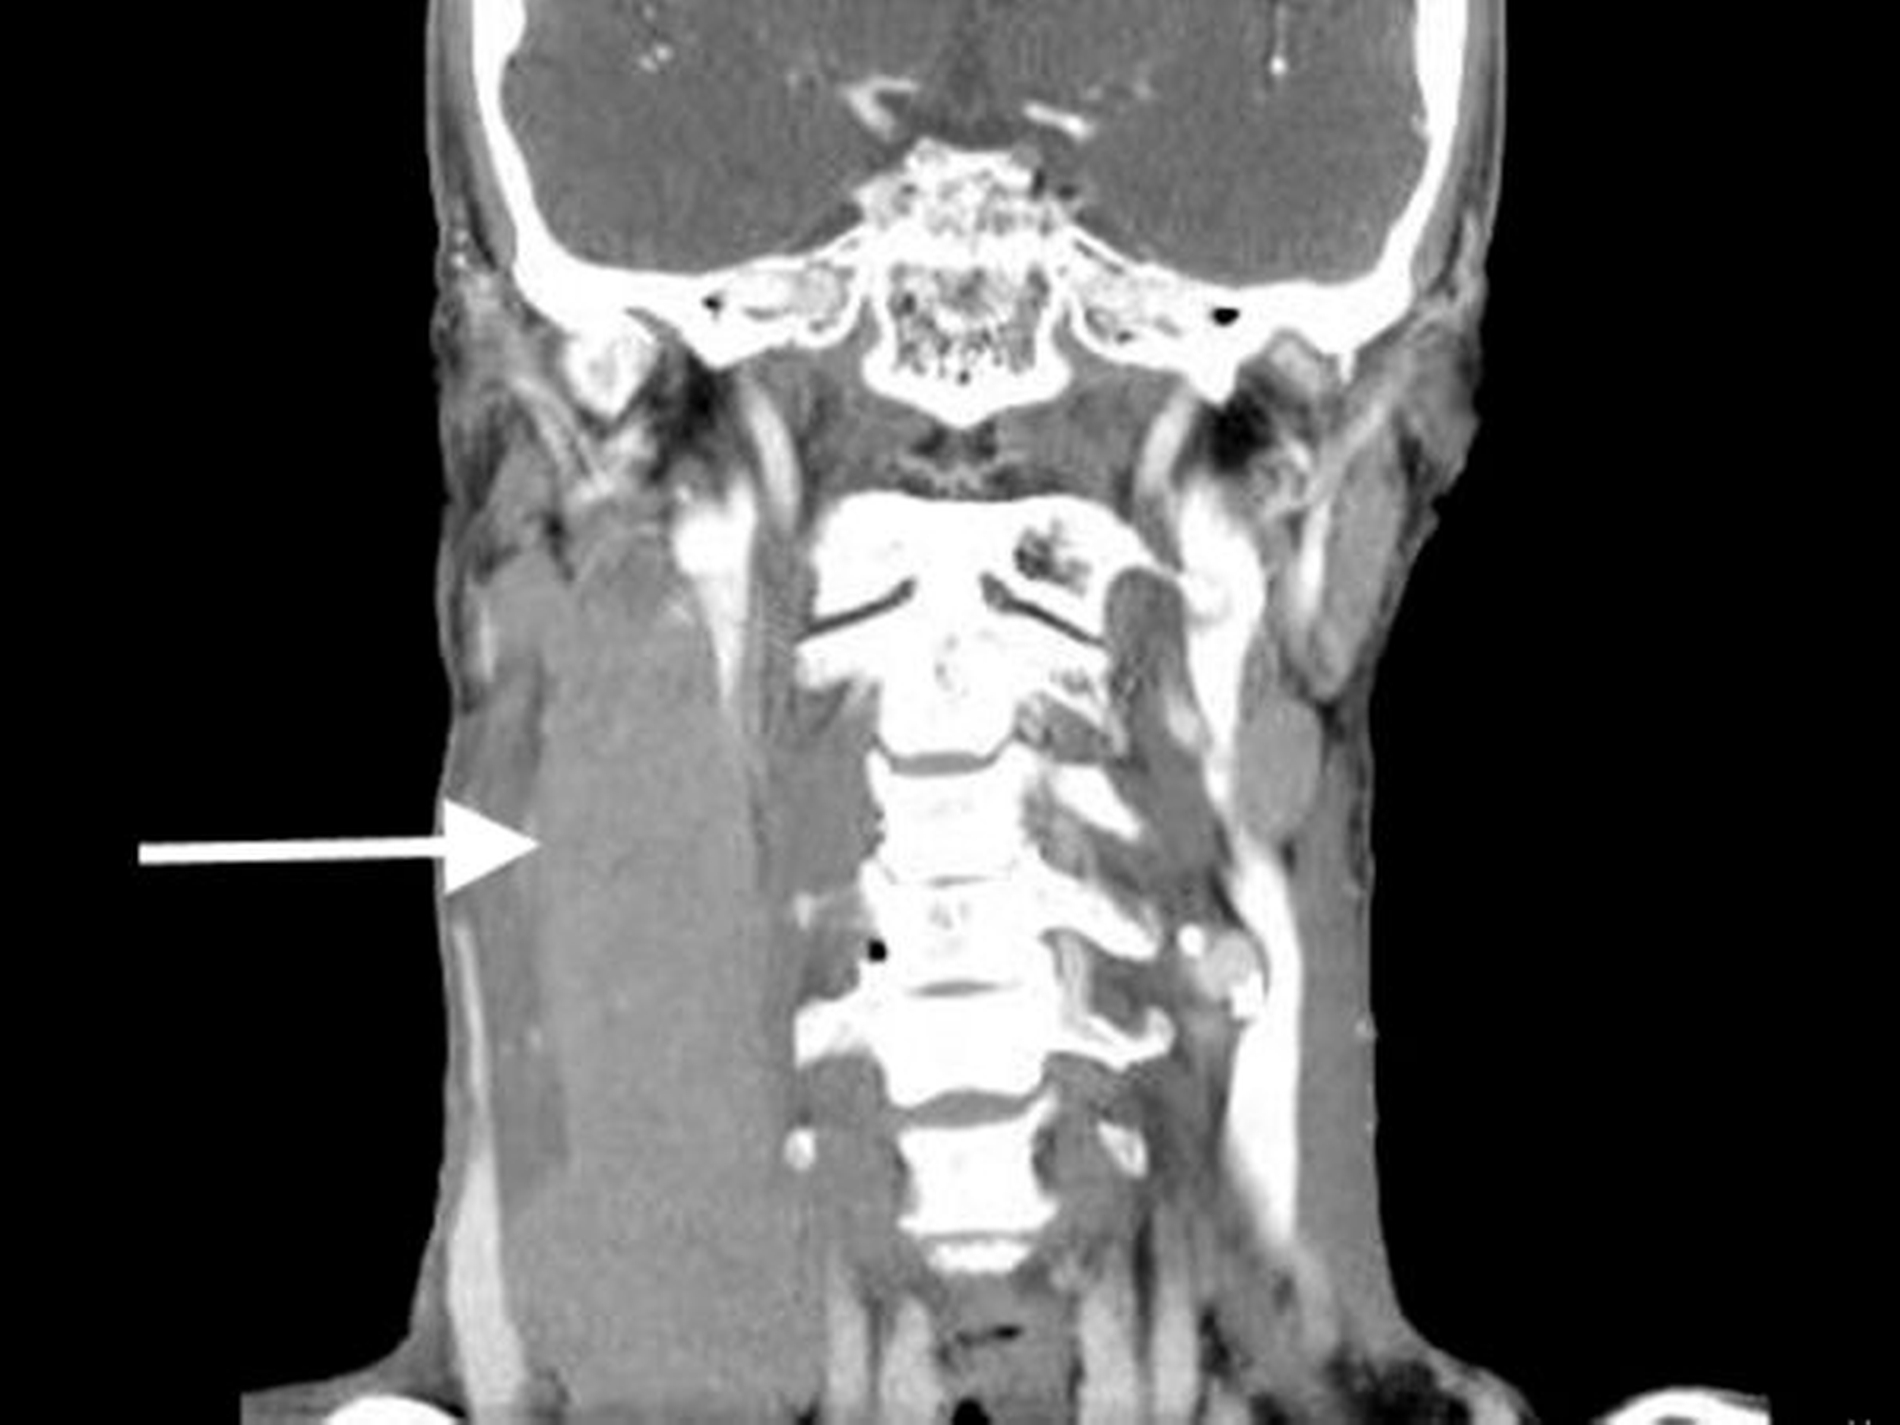

Der Knochen war arrodiert. Daneben zeigten sich ausgedehnte pathologische Raumforderungen cervical rechts vom Unterkieferrand bis nach supraklavikulär reichend unter Einbeziehung der Nervgefäßscheide (Abbildung 3b) bei unauffälligem cranialem CT.